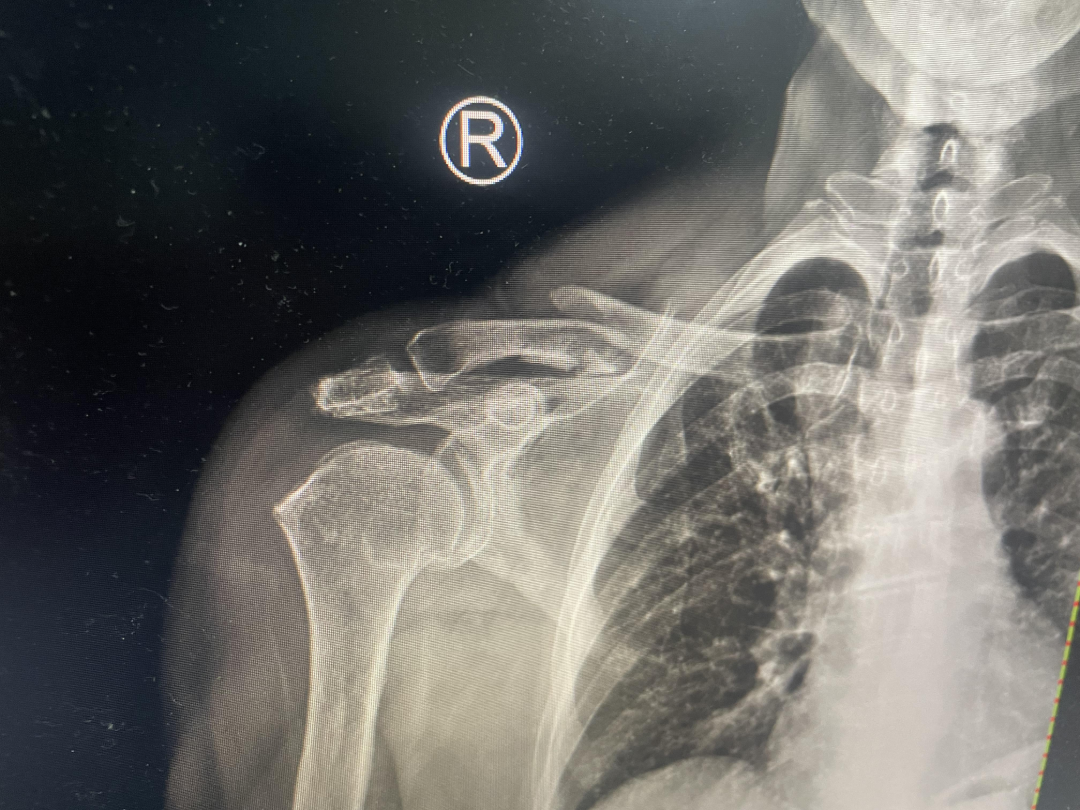

据悉,患者因不慎摔伤,导致右肩部出现剧烈疼痛,伴随活动受限。受伤后,患者第一时间前往附近医院就诊,经CT检查显示锁骨中段连续性中断,骨折断端重叠且呈粉碎性改变,接诊医生评估后建议住院进行手术治疗。患者家属考虑到手术存在创伤大、恢复周期长等问题,随即辗转来到西安市红会医院手法复位室,寻求保守的治疗方案。

复位后的影像学检查可见,骨折断端对位对线良好,重叠移位完全纠正,骨折形态恢复正常,无创治疗达到了理想的复位效果。整个治疗过程无需切口、无需麻醉,全程无创,患者在治疗中痛感轻微,极大减轻了身心负担。